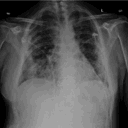

pulmones coronavirus.jpg